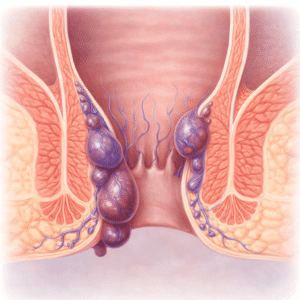

Peräpukamat

Mitkä ovat peräpukamat? Peräpukamat ovat turvonneita verisuonia peräaukon tai peräsuolen…

Peräpukamien helpotus: Kotikonstit ja ehkäisyvinkit

Peräpukamat vaikuttavat miljooniin ihmisiin ympäri maailmaa, mutta ne ovat edelleen tabuaihe. Ne…

Peräpukamien helpotus ja ehkäisy